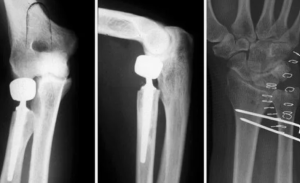

Операция проведена в плановом порядке 11.07.2024. Первым этапом выполнен хирургический доступ по Кохеру к головке лучевой кости. При доступе обнаружено застарелое повреждение локтевой латеральной коллатеральной связки локтевого сустава с дегенеративным изменением волокон. Головка лучевой кости удалена. Установлены примерочные компоненты головки и ножки эндопротеза для компенсации длины потерянной костной ткани. Импактирована цементная ножка протеза с модульной головкой 24-12 мм (ChM, Warsaw, Poland) (рис. 3). Следующим этапом выполнен рентгенологический контроль лучезапястного сустава (рис. 4, а), проведены доступ в нижней трети предплечья, укорачивающая корригирующая остеотомия локтевой кости с фиксацией титановой пластиной АО LCP, пластика дистального лучелоктевого сочленения плетеной нитью FiberWire (Arthrex, Naples, FL, USA) по Адамсу - Бергеру (рис. 4, б) [17, 18]. Дополнительно дистальное лучелоктевое сочленение фиксировано спицей Киршнера.

Последний этап — аутопластика локтевой латеральной коллатеральной связки с помощью фрагмента апоневроза трехглавой мышцы плеча с фиксацией титановыми анкерами Corkscrew (Arthrex) к плечевой и локтевой костям (рис. 6). Проведен рентгенологический контроль (рис. 7). После операции наложена гипсовая иммобилизация от верхней трети плеча до головок пястных костей в положении в локтевом суставе 90° и разгибания кисти 15°.